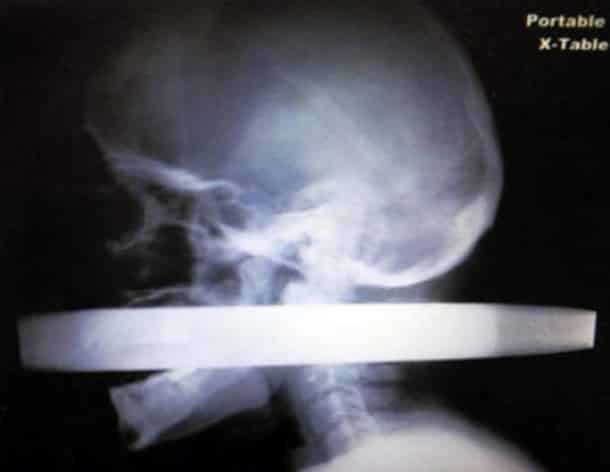

33 radiographies qui prouvent que les gens font des choses douteuses avec leur corps !

Accident, incident de pistolet à clous ou introductions douteuses de choses douteuses dans des parties douteuses de leur corps…voilà un petit aperçu de ce que voient les médecins au quotidien…

Certaines radiographies sont impressionnantes mais relèvent d’accidents…d’autres en revanche…